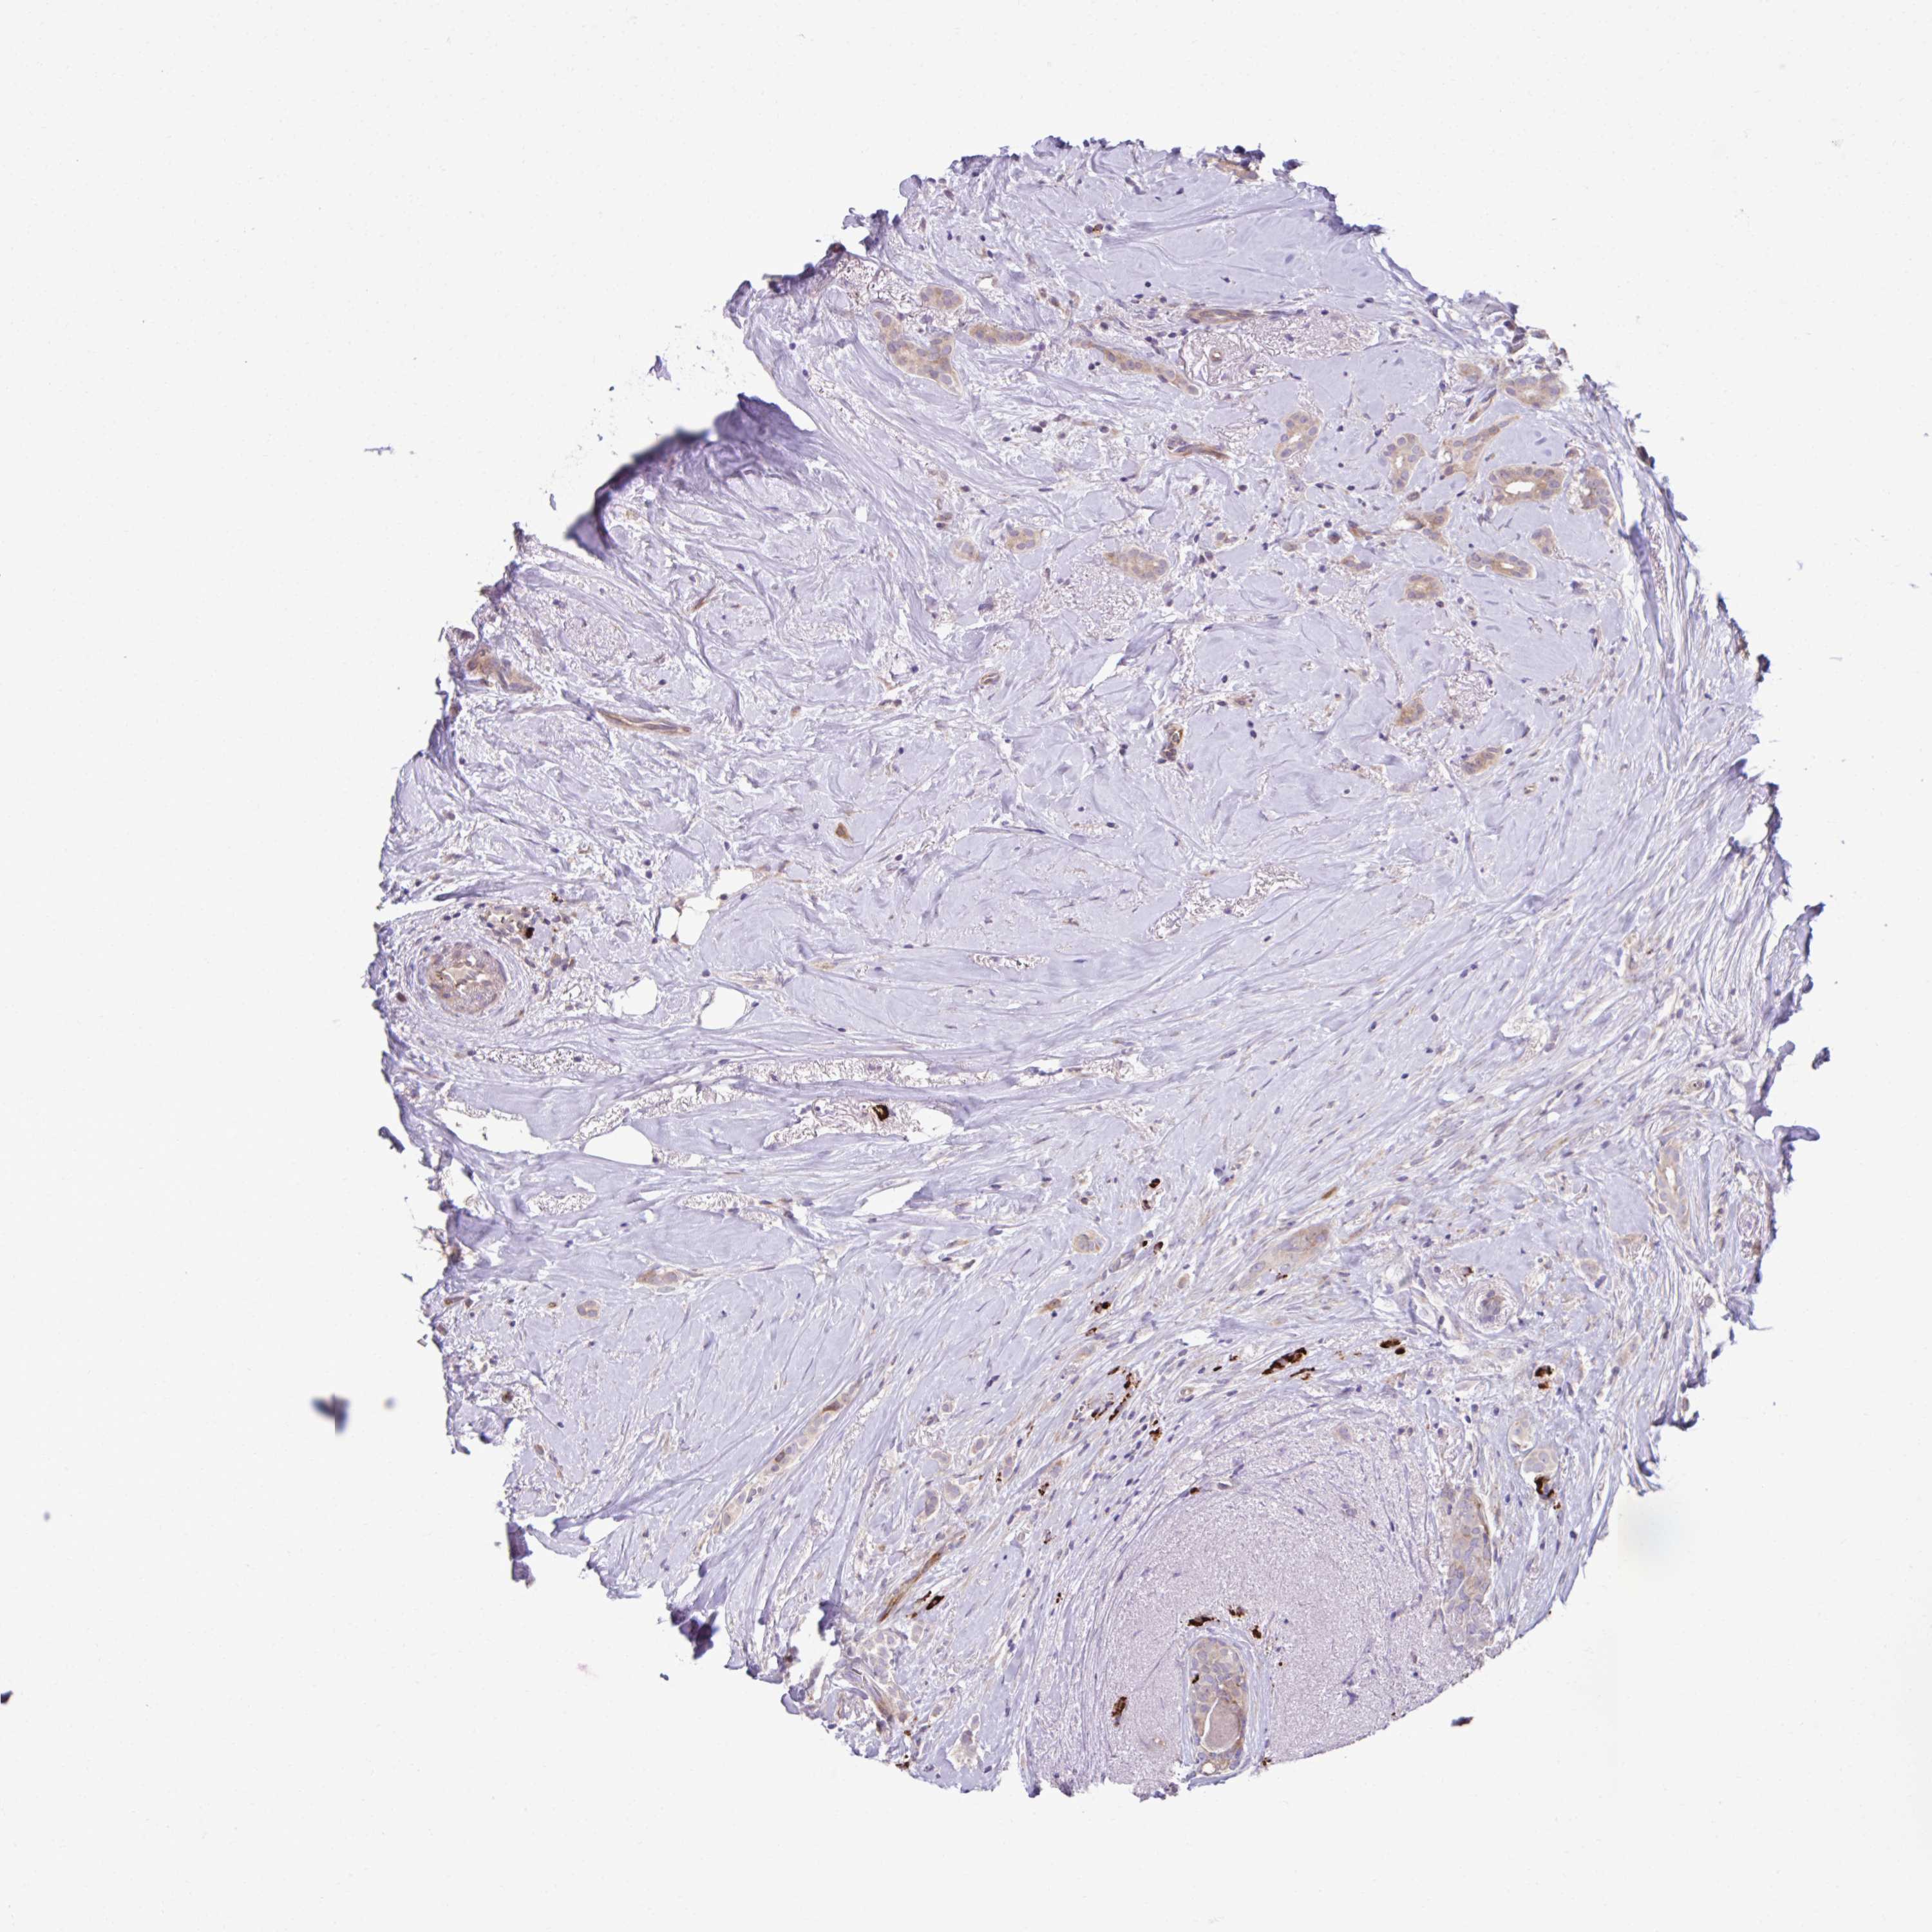

CANCER BREAST CANCER Show tissue menu

Breast cancer

Human cancer